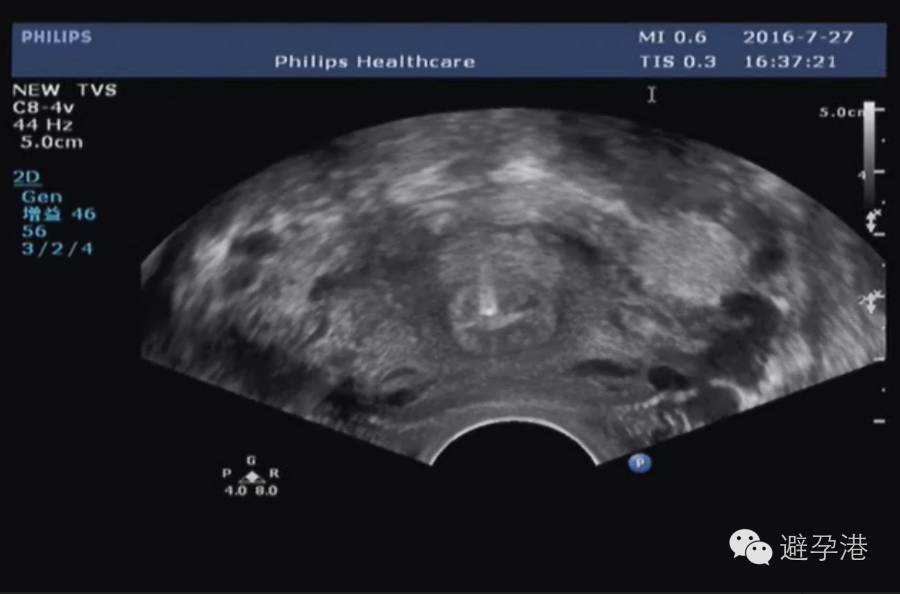

3.横切面:宫底和宫体切面可见点状强回声光斑。

吉妮致美环怎么样吉妮致美节育器超声图像解读_https://www.jmylbn.com_新闻资讯_第6张